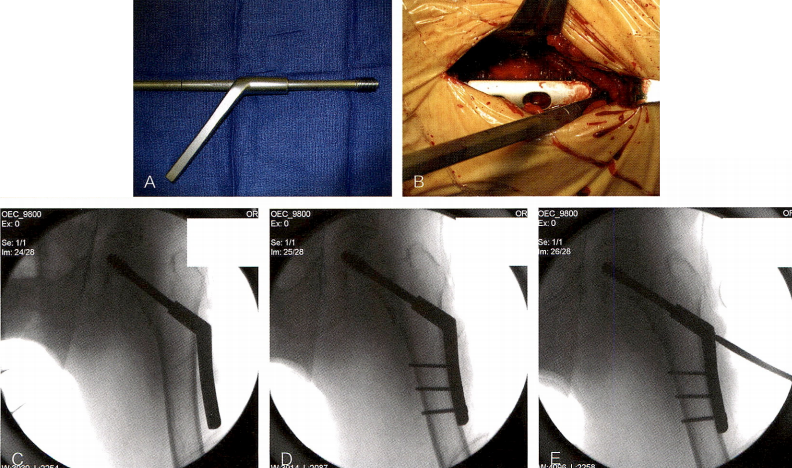

2、导针引导动力髋螺钉和骨折复位:

显露股骨近端外侧骨皮质后,开始选择导针进针点。钢板的导针进针点位于股外侧肌嵴下方,正对小转子中点,平臀大肌股骨止点处(技术图2)。导针的进针点需要依据实测的颈干角大小调整,以135°为起点,每相差5,导针进针点也需相应地上移1cm(小角度装置),或下移1cm(大角度装置)。要评估股骨前倾角。可以先贴着股骨颈前皮质表面插人一枚导针,妥置于股骨头的前方。或者,若牵引床附有专用支架,可以利用股骨颈与支架的位置关系,借助影像学摄片在股骨颈内正确置入导针。切口远端长度要足够长,以便能将钢板放入。

技术图2 导针定位及调整。A.X线显示导针位于小转子水平,恰好在股外侧肌嵴下方。B.经角度导向器打入一枚导针,与前方的导针平行,显示出股骨的前倾。C.X线显示前倾导针和已插入的导针。D.导针在正位上位于股骨头中央。E.导针在侧位上位于股骨头中央,注意支架的位置,以其为参照能直接引导导针往上方进入股骨颈。F.三联扩孔器。

在导针的置入点放置角度导向器,位于股骨干中央,并与外侧皮质平齐。相比于徒手打入导针,更推荐借助角度导向器打人,这样在加压侧方钢板时,可以避免钢板以外侧皮质为支点产生杠杆效应。在正、侧位透视引导下置入导针,确保其置入股骨头的中心位置。若导针在正、侧位上均不位于股骨头中心,则必须拔出后重置。需重新评估骨折复位,调整导向器位置以确保导针置入股骨头中心。正、侧位片上导针顶点距离关节线均应<5mm。使用器械配套的测深器测量导针进入骨内的深度。需慎重选择拉力螺钉的长度,尤其是在强力牵引下才得以复位的高度不稳骨折类型,该牵引力量可能导致骨折端分离,从而在测量时高估拉力螺钉的长度,并在牵引力最终松开时导致螺钉尾部突出。导针需深达软骨下骨,以减少扩孔后导针松动或不小心插人过度。

对于不稳定的骨折或通过过度牵引后得到解剖复位的骨折,需在首枚导针的近侧打入第二枚导针于股骨头内。这枚导针起到防旋作用,可以确保在扩孔和置钉时,近端的头颈骨块不发生旋转。三联扩孔器被用来在外侧皮质、股骨颈、股骨头为拉力螺钉开槽扩孔。扩孔的深度比此前测得的拉力螺钉长度短5mm,以确保扩孔时不伤及股骨头的软骨下骨。透视引导下进行三联扩孔器钻入和拔出的操作。扩孔时的透视引导很重要,这样可以确保导针不跟钻头一起打转并在无意间穿入骨盆。扩孔至预计深度后,拔出扩孔器,注意导针不要被带出。使用工具顶住导针可有助于防止其退出。有时扩孔可能会导致股骨近端外侧皮质骨折,骨折发生后会演变为横行或反斜行(AO/OTA 31-A3型),此时若仅用动力髋螺钉固定,会进一步引起骨折端复位丢失和错位。对于这些病例,股骨近端的外侧壁可以使用转子稳定钢板联合动力髋螺钉进行固定,或者也可以改用髓内固定系统来固定骨折。